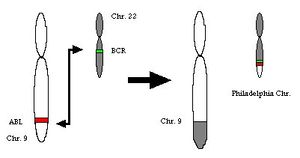

تم اكتشاف كروموسوم فيلادلفيا (كروموسوم 22) في عام 1960 بواسطة عالمين أميركيين من مدينة فيلادلفيا، حيث تم ملاحظة أن العديد من المصابين ( 70%-90%) بهذا المرض مصابين باضطراب وراثي خلوي متمثل بانتقال مكاني بين الكروموسومين 9 و 22 مما ينتج اتحاد جيني بين الجين BCR الموجود على الكروموسوم 22 و الجين ABL الموجود في الكروموسوم 9 لإنتاج بروتين حجمه 210 كيلو دالتون، يعمل عمل إنزيم تايروسين كاينيز. يعمل هذا البروتين على تحفيز بروتينات أخرى عن طريق نقل الإشارة لها علاقة بتصليح أعطاب الدنا و دورة حياة الخلية و تثبيط استموات الخلايا مما يجعلها سريعة الإنقسام و التكاثر.